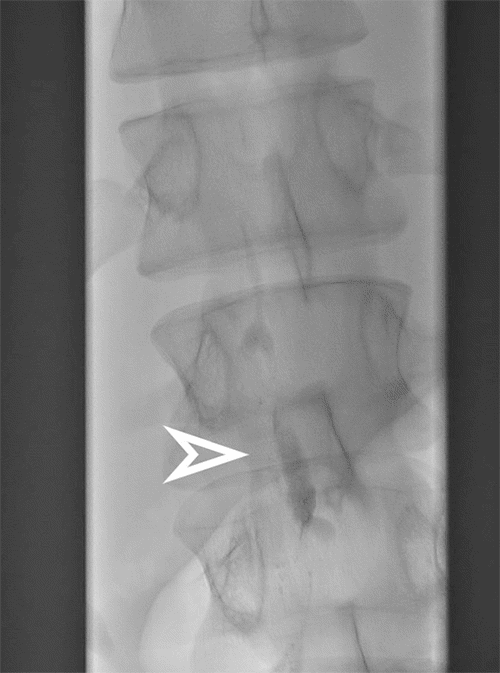

Interventional radiology performed a lymphangiogram to evaluate lymphatic drainage of the pelvic, abdominal, and thoracic regions. The study identified active extravasation from the thoracic duct near the clavicular head. The interventional radiologist then embolized the leaking segment using coils and glue (Figures 3-6). While chest tube drainage briefly declined, it returned to pre-procedure levels by postoperative day 2.

Figure 3. Early Filling of Cisterna Chyli over L1 (arrow). Published with Permission

Figure 4. Lymphangiogram via Inguinal Lymph Node Cannulation Demonstrating Opacification of Lumbar Nodes, Cisterna Chyli, and Lower Thoracic Duct. Published with Permission